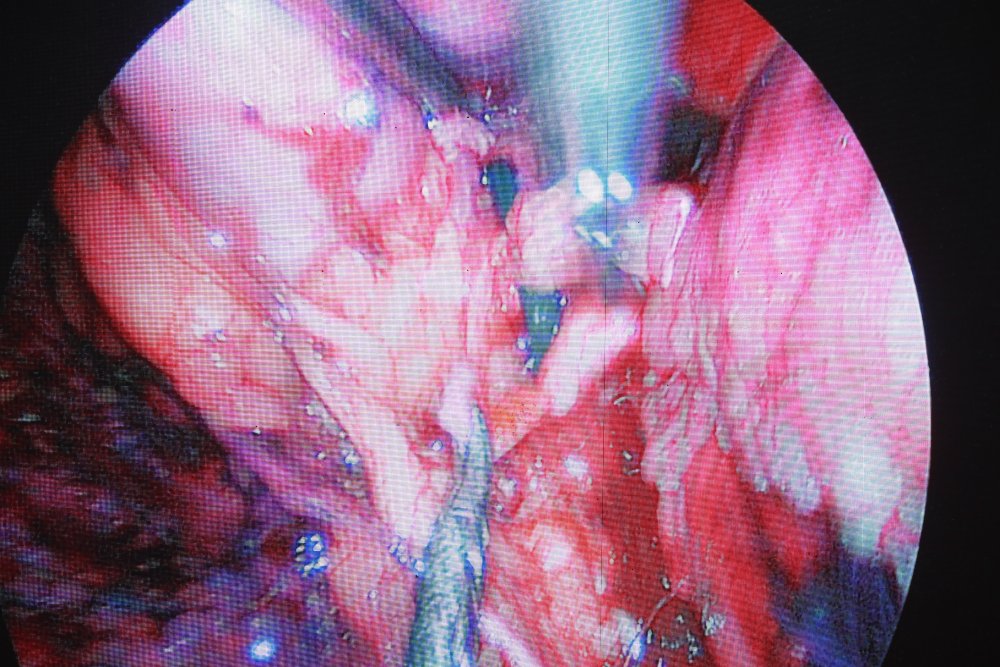

- Мэс заслын өрөө-1: Хэвлийн дурангаар бөөрийг бүхэлд нь авах мэс засал

- Мэс заслын өрөө-2: Хэвлийн дурангаар бөөрийг нөхөн сэргээх мэс заслыг БНСУ, БНХАУ-ын эмч, мэргэжилтнүүд хийж дуусгалаа.

- Мэс заслын өрөө-1: Хэвлийн арын зайгаар дурангаар бөөрийг нөхөн сэргээх мэс засал

- Мэс заслын өрөө-2: Бөөрний чулууг хатгалт-дурангаар авах мэс заслыг ГАДААД болон ДОТООДЫН эмч нар хамтран хийж байна.